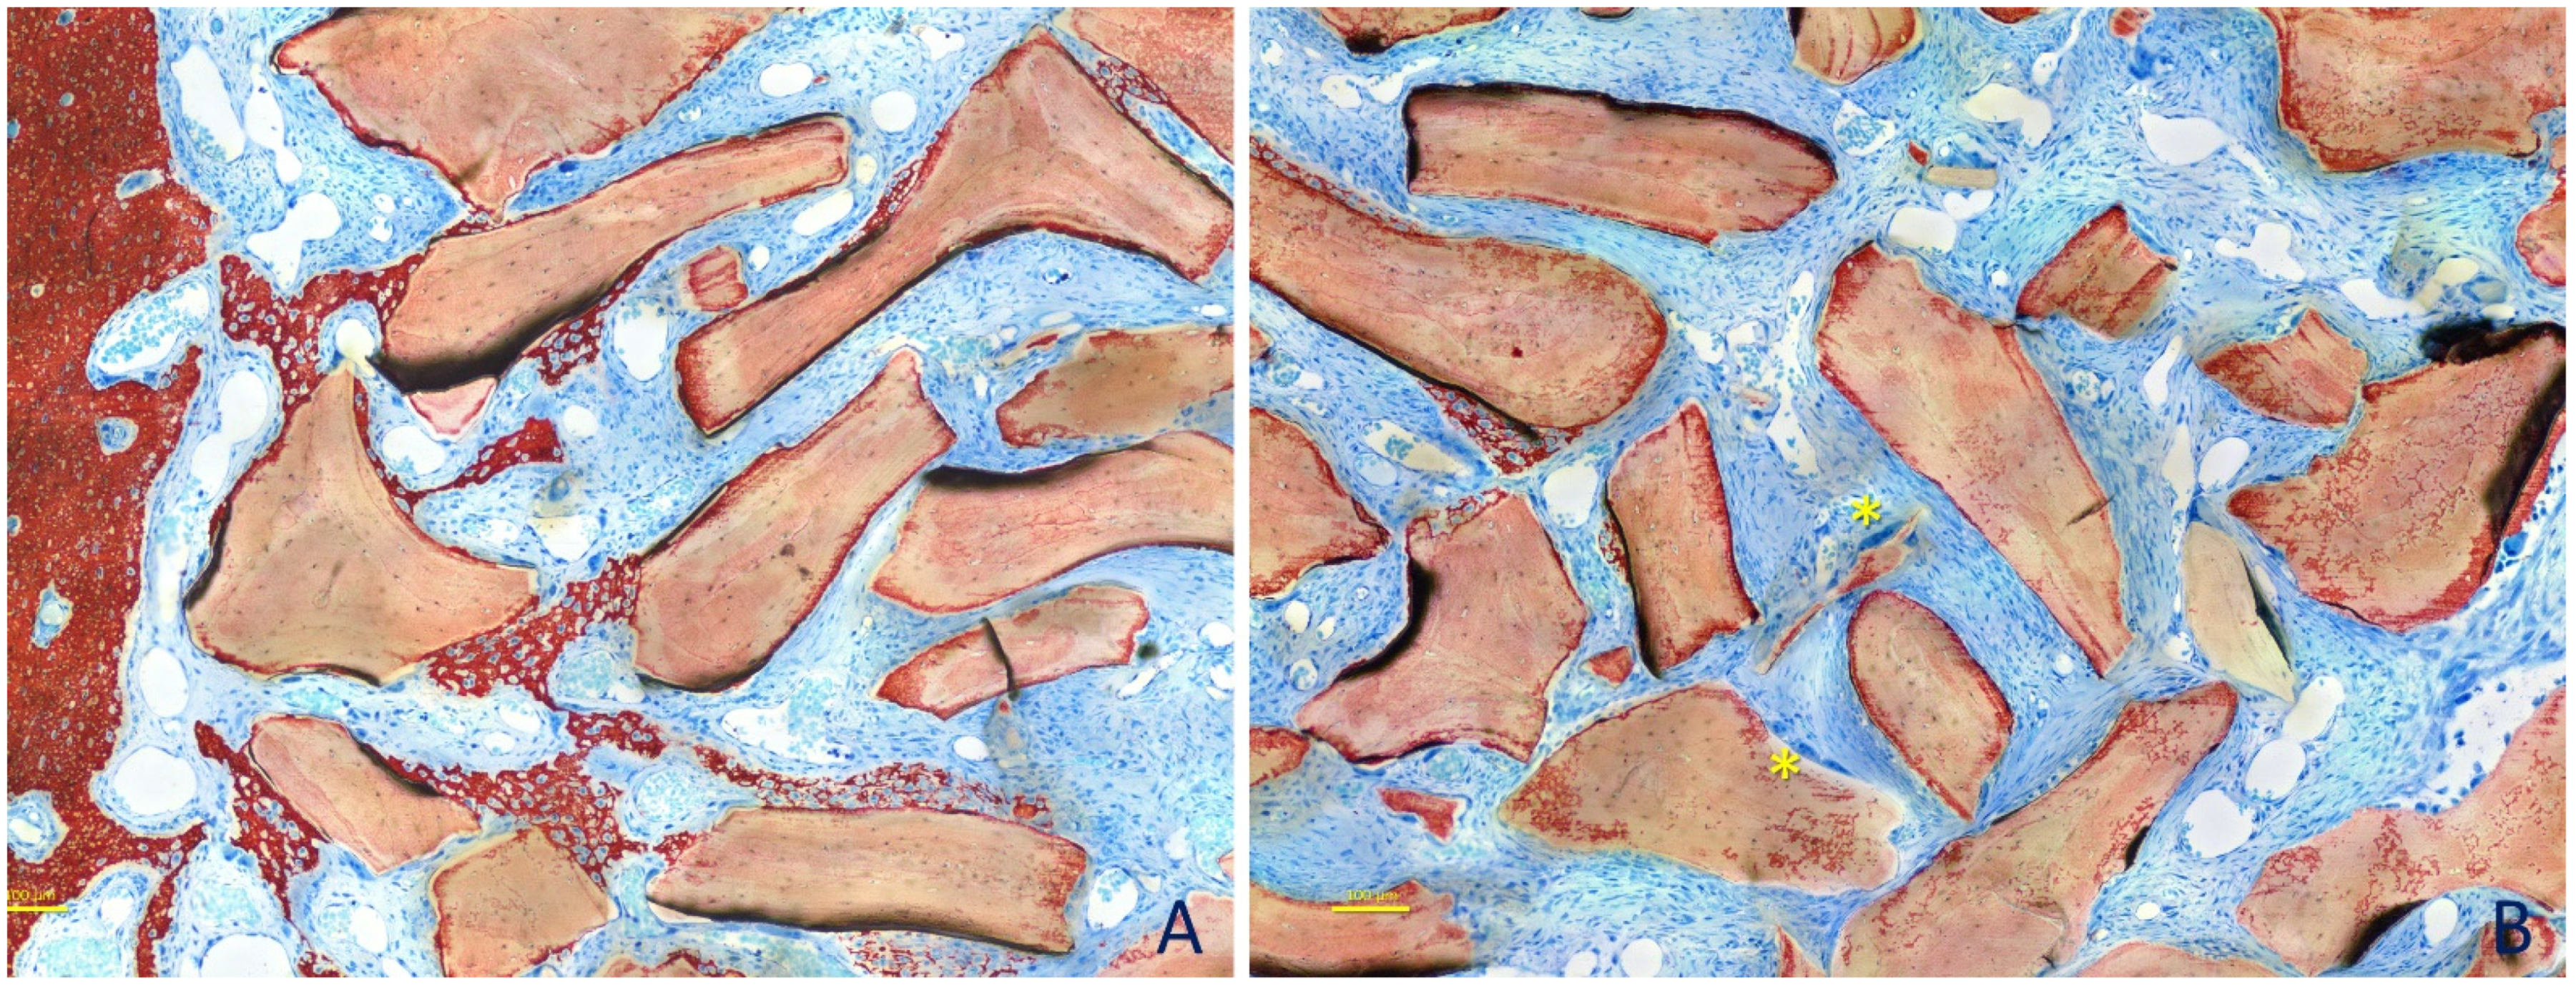

3. Results